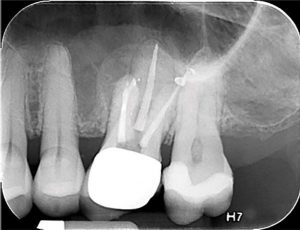

Eighteen months later, the patient returned for a second reassessment appointment (Figure 4 ). Tooth LR2 was slightly sensitive to percussion and the overlying gingival tissues were inflamed.

The patient was referred for a CBCT; the scan (Figure 5)

revealed a common area of rarefying osteitis surrounding the mesial buccal and distal buccal roots which had caused elevation of the sinus floor. As the endodontic pathology had not resolved, treatment options were proposed. The patient chose to have microsurgical therapy performed.